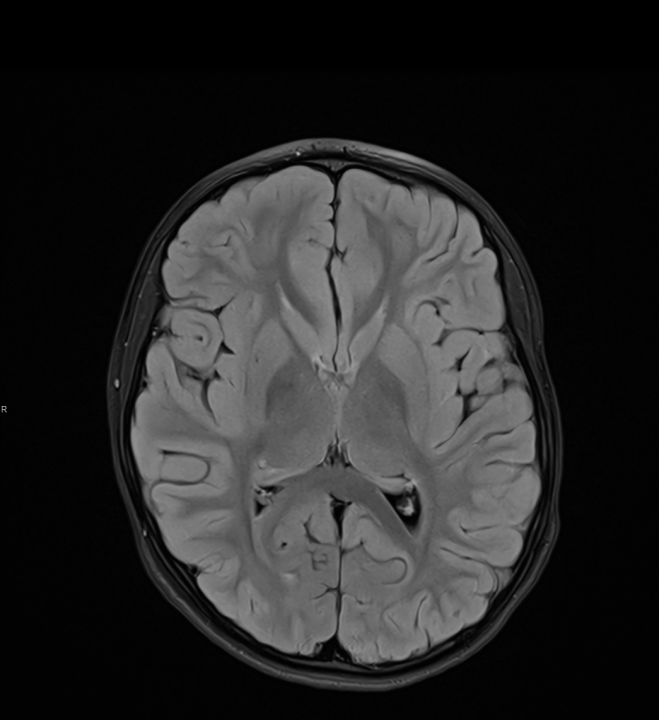

Tijekom Tjedna mozga Poliklinika Affidea Vita daje 20 posto popusta na magnetsku rezonancu!

Povodom obilježavanja Tjedna mozga od 11.

tjedan mozga

MR mozga

MR angiografija